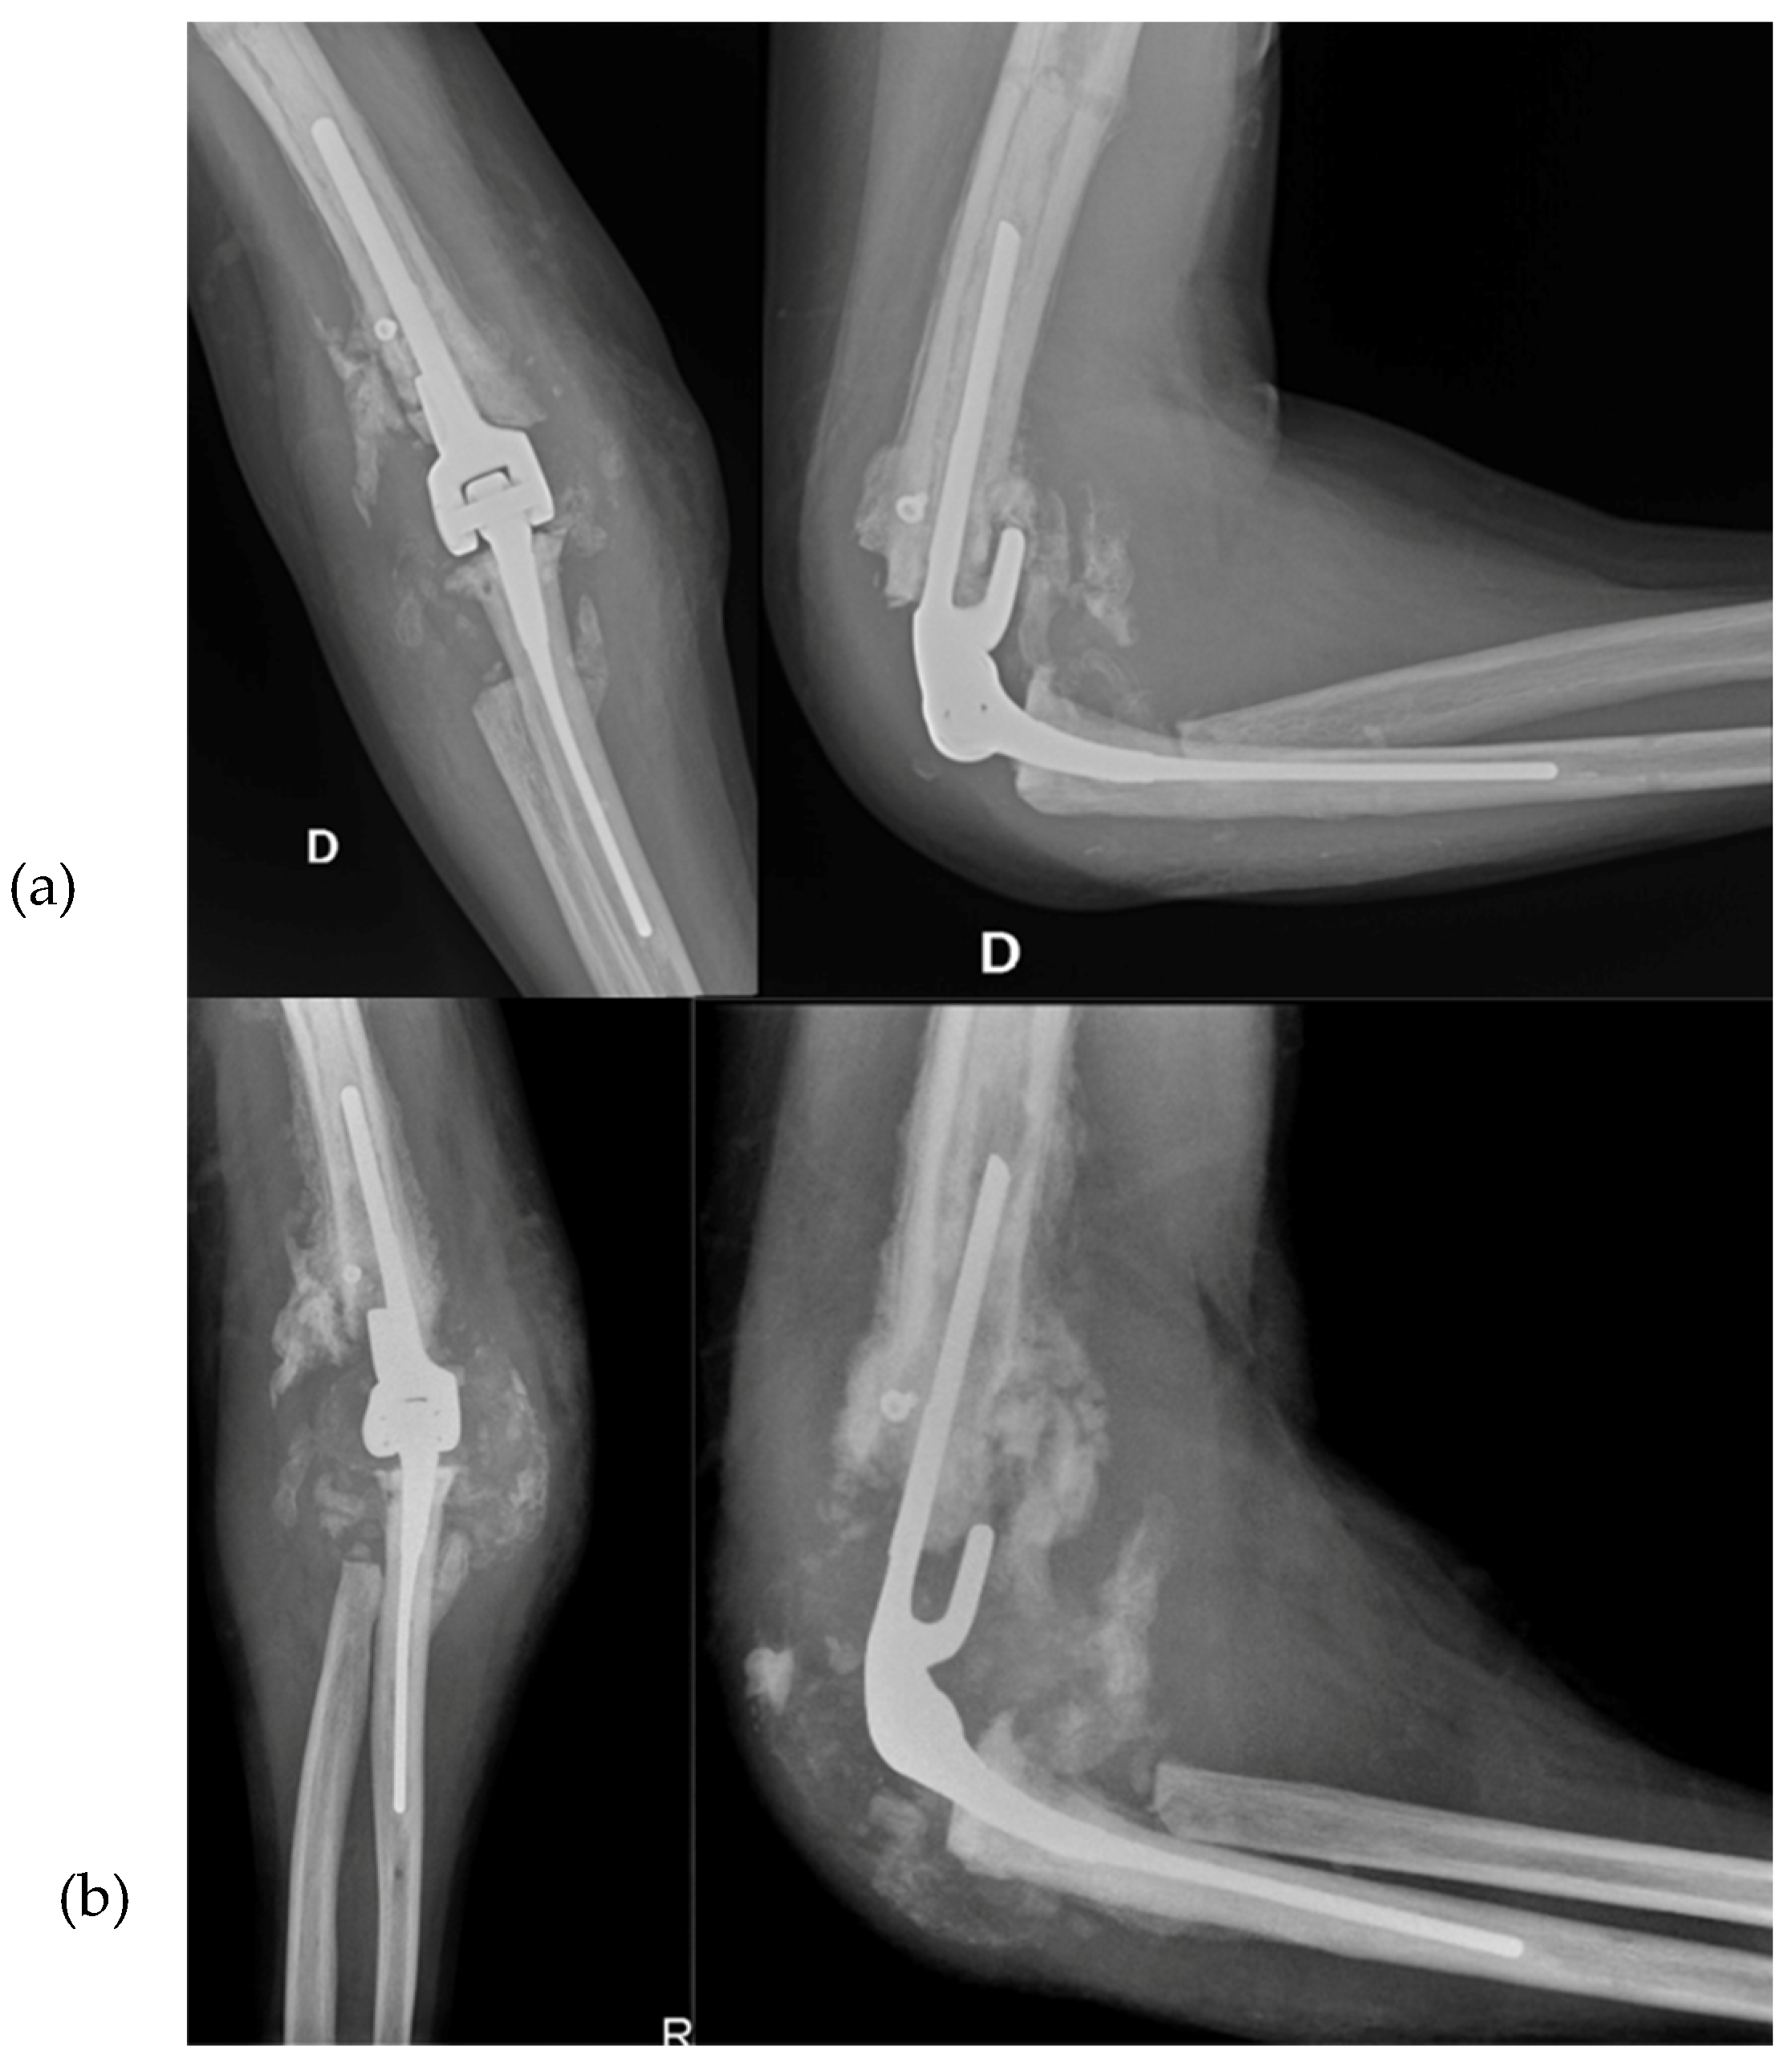

2.4.4. Arthrodesis

In early August 2013, a surgical procedure was performed to fuse the elbow joint using a plate with 12 holes and a 90-degree flexion angle, using the same surgical access point as the previous surgery (Figure 4). During the procedure, it was observed that the anatomical structures of the ulna, radial head, and distal humerus were severely distorted and not recognizable. A new synovectomy and osteotomy were performed to apply the plate. After discharge from the hospital, the patient was instructed to wear a brace at 90 degrees and an arm sling, undergo physiotherapy to mobilize the fingers and wrist, and have an X-ray examination 30 days after the surgery.

At the 30-day postoperative follow-up, X-rays revealed three broken screws in the proximal humeral shaft and a subtle periosteal reaction around the plate. The patient was provided with a new brace and referred for a fixation revision. The screws and plates were removed using the previous lateral elbow access from the surgery. The broken screw bodies and heads were left in place since they were embedded in the bone and soft tissue, respectively. However, due to the last 7 to 8 cm of the distal humerus appearing like a cortical lamina, internal fixation was not feasible. Consequently, an external fixator bar-to-bar was applied after the arthrodesis surfaces were prepared. A follow-up X-ray confirmed the device's appropriate positioning (Figure 5). At hospital discharge, the orthopedic recommendation was to wear the external fixator for 60 days, rest, and undergo weekly ambulatory assessments of the local clinical findings.

Figure 4. Post-arthrodesis X-Ray anteroposterior and lateral views of the right elbow. (a) Post operative images. (b) 30 days after images.